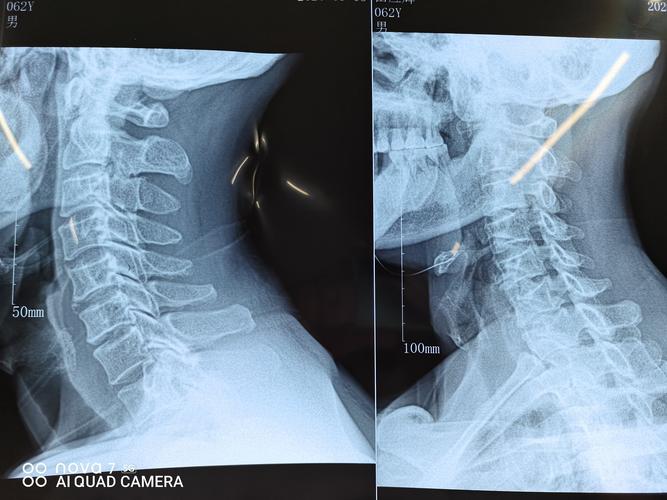

颈椎正侧位

颈椎正侧位,颈椎正侧位报告模板

术前颈椎正侧位片,见颈椎蜕变,局部骨质增生.

颈椎正侧位片

颈椎正侧位x光片

1. 颈椎的生理曲度 正常人的侧位片可见颈椎生理性 前凸.